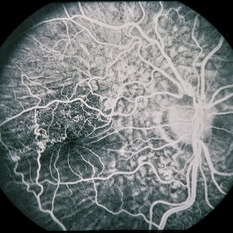

45-year-old Hispanic male with hypotony from over-filtration.